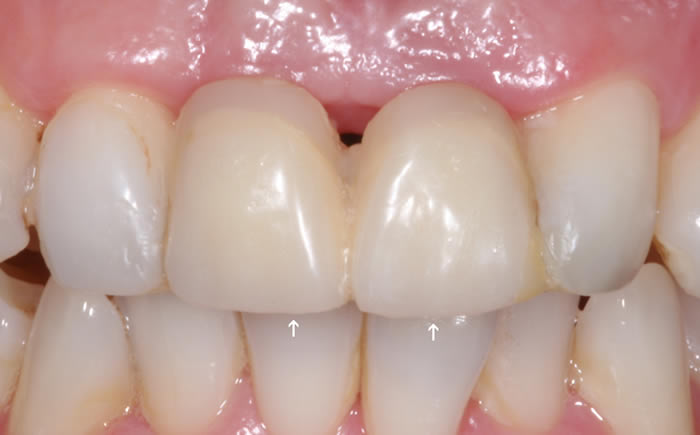

More front teeth replaced by dental implants

Case Three (4 images)